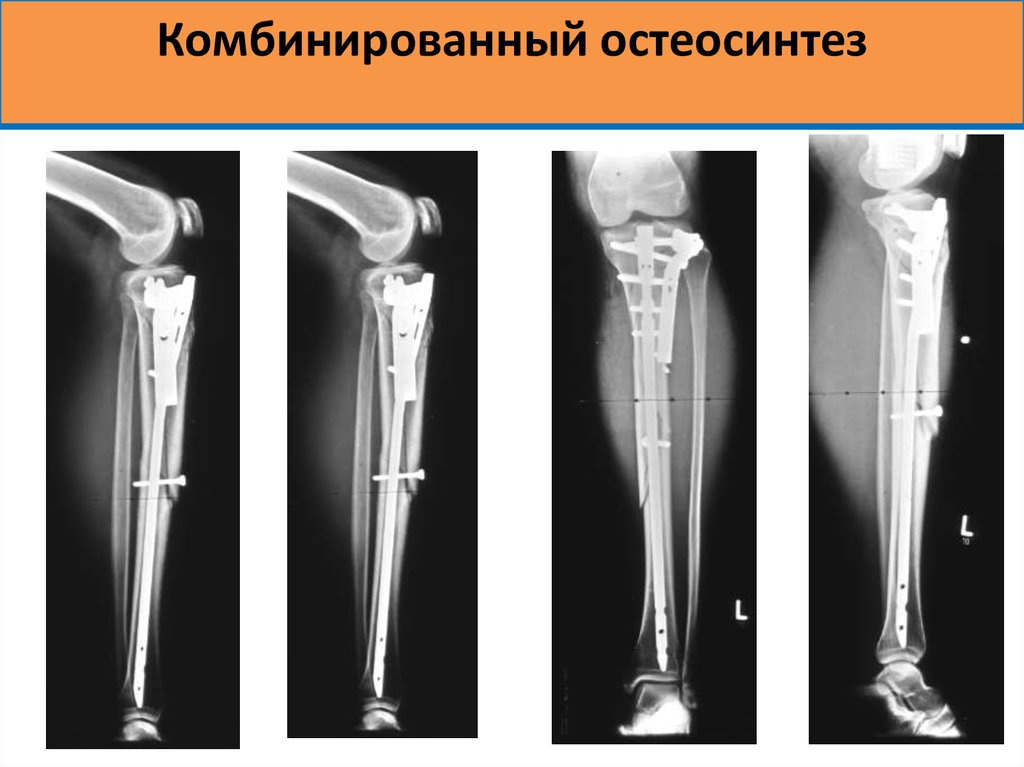

В зависимости от клинической картины, остеосинтез плечевого сустава может быть экстрамедуллярным (с применением пластин) или интрамедуллярным (с использованием спиц). Эти две разновидности операций относятся к группе внутренних, то есть погружных. Для фиксации отломков в этом случае могут использоваться винты, спицы, штифты, пластины, проволока. Внешний (чрескожный) вариант – это установка аппаратов внешней фиксации, самый известный – аппарат Илизарова.

Операция проводится при поперечных переломах костей с достаточным объемом костномозговой полости. Для более прочной фиксации используют штифты с отверстиями для винтов, которые проводят через кость. Это БИОС, то есть блокированный интрамедуллярный остеосинтез. Также используются самоблокирующиеся штифты Fixion. Они позволяют сделать операцию максимально быстро и используются даже при оскольчатых переломах.

Операции с использованием пластины при переломе плеча

Это накостный вариант хирургического вмешательства. Титановые пластины, устанавливаемые в плечо, различаются по длине, ширине, толщине и форме, что позволяет подобрать оптимальный вариант. К кости пластина крепится винтами. Передовая разработка – фиксаторы с угловой и полиаксиальной стабильностью. В отверстиях пластин и головках винтов есть резьба, за счет этого шляпки винтов фиксируются очень прочно, повышая стабильность костного синтеза.

Аппараты внешней фиксации (чрескожная методика)

Методика позволяет репозиционировать и тщательно зафиксировать отломки, не обнажая область перелома.

Ее суть – проведение через костную ткань стержней или спиц, фиксирующихся снаружи в специальном аппарате. Сейчас есть монолатеральные, циркулярные, секторные, полуциркулярные, билатеральные и комбинированные аппараты. Предпочтение чаще отдается стержневым моделям. Использование внешних фиксаторов – незаменимый способ лечения высокоэргичных травм, например минно-взрывных, огнестрельных, которые сопровождаются значительными повреждениями как костей, так и мягких тканей. Периферическое кровоснабжение конечности должно быть сохранено.